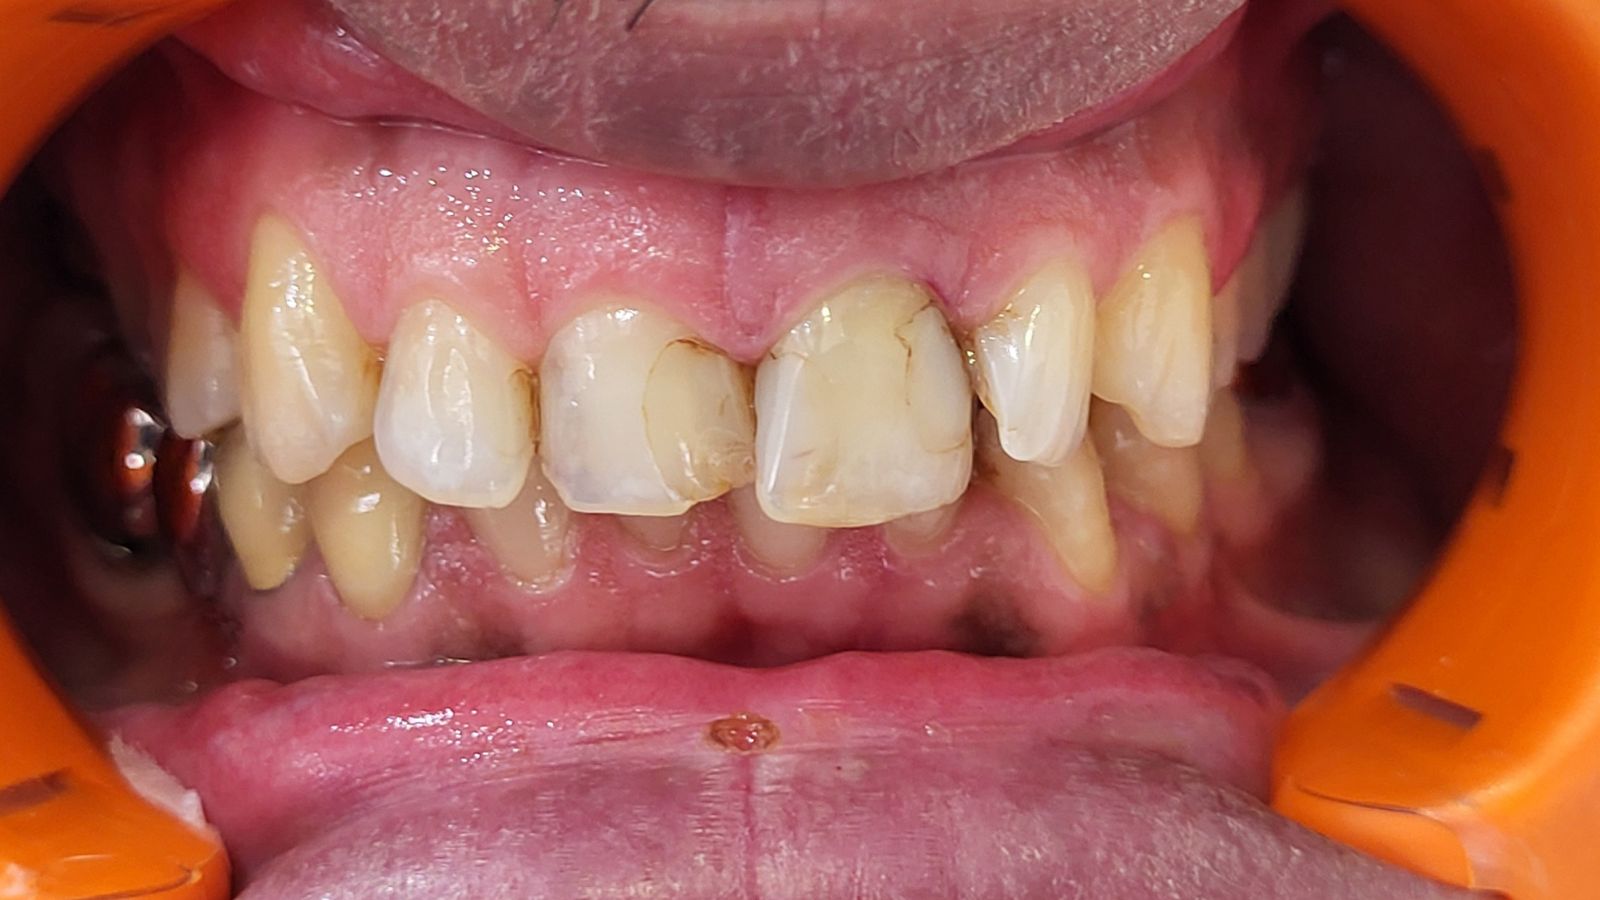

Réhabilitation complète avec mise en charge immédiate (4 implants bas / 6 implants haut)

Le patient se présente avec des dents qui bougent, en haut et en bas.

Nous avons commencé par la mâchoire inférieure avec 4 implants et une mise en charge immédiate.

Trois mois après, le haut a été fait avec le même principe avec 6 implants.

Cette fois-ci, il existait un déficit osseux, résolu par une technique d’expansion sans avoir recours à la greffe d’os.

Les prothèses réalisées sont vissées, ce qui permet de les enlever, les nettoyer une fois par an, ou résoudre n’importe quel problème.

Images :